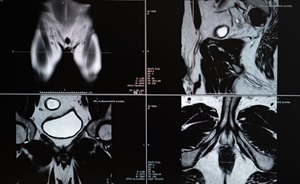

High-resolution MRI has been a game changer for diagnosing prostate cancer and preventing unnecessary biopsies.

Hackensack Meridian urologists have led at the forefront as imaging technology for prostate cancer has advanced. Compared with other MRI technology, our 3 Tesla (3T) MRI is unmatched in creating detailed, 3D images of the prostate.

Our 3T MRI makes a difference by allowing your care team to:

- Determine with great precision the size and stage of any tumors in the prostate.

- Distinguish low-risk tumors that are candidates for active surveillance without biopsy.

- Identify more aggressive tumors for biopsy and treatment.

- Detect any cancer that has spread beyond the prostate.

- Fuse high-resolution, 3D images with ultrasound for precise biopsy.